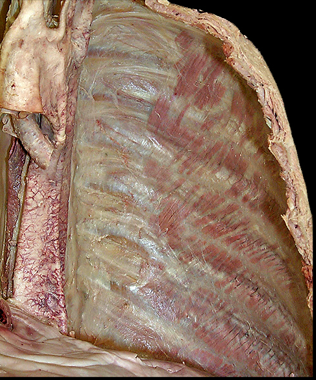

External intercostals (E)...inspiration...most superficial

Internal intercostals (I)...expiration

Innermost intercostals (IM)...elevate?…not completely understood...most deep

what is between the internal intercostals and the innermost intercostals? which muscle is on top?

when looking at a picture how do you identify these muscles, what should you look for?

BV's and nerves in between them

internal intercostal on top

basically, look for the innermost muscle and if its muscle colored it is the innermost intercostals...if it looks like a layer was peeled and you see nerves traveling horizontal, it indicates that you are looking at the internal intercostals

what muscle do you see here and how do you know?

innermost intercostals because you can see the nerve and vessels driving into the muscle indicating that you can see the innermost intercostals (you are looking inside the chest so the IM are the deepest muscles inside)